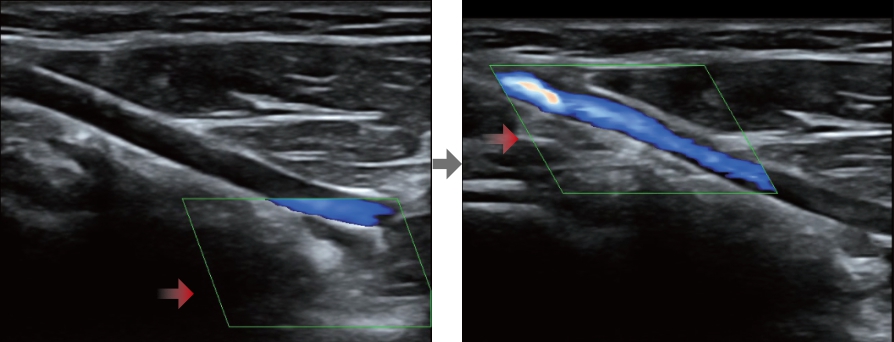

Smart Track

Smart Track bietet eine schnelle und intelligente Optimierung f├╝r die vaskul?re Bildgebung mit einer einfachen One-Touch-Aktion. Es kann Farbe, Leistung und das PW-Spektrum optimieren durch Self-Tracking und zeitintensivere Schritt reduzieren. Deshalb ist der Workflow der vaskul?ren Untersuchen mit einer optimalen Ansicht vereinfacht.